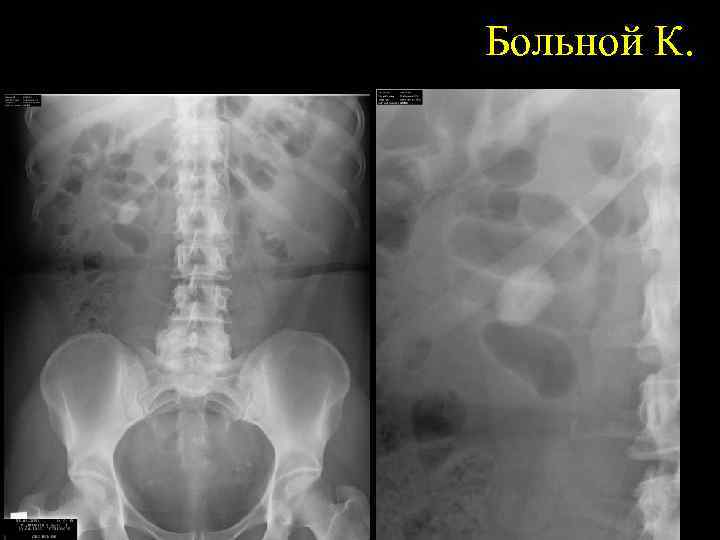

Больной К.